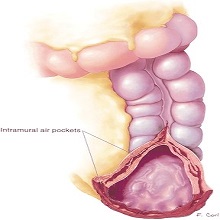

Исхемијски колитис је оштећење сегмената дебелог црева, које настаје као последица мезентеричне васкуларне оклузије. |

Дивертикулуми танког црева су локализована проширења цревног зида која су у вези са луменом црева. |